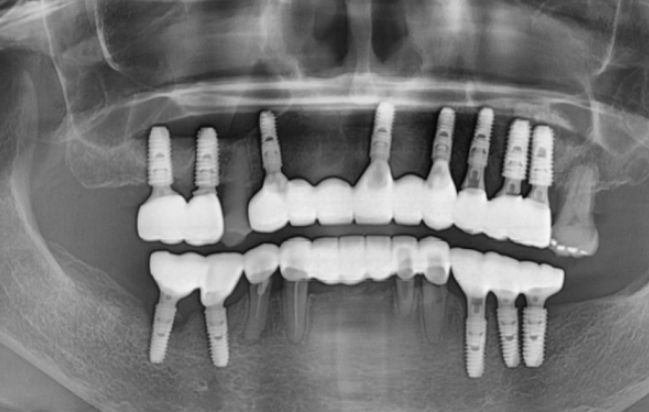

디지털 기술을 사용하여 가이드를 제작하고

모의 수술을 진행하면

당일 전악 임플란트 수술도 가능합니다.

식립할 임플란트의 사이즈, 두께, 길이

위치까지 분석을 해주니

전악 임플란트 수술 시 요긴하게 사용하고 있습니다.

이를 뽑고 일주일 뒤

하루에 위, 아래 임플란트 수술을 진행했습니다.